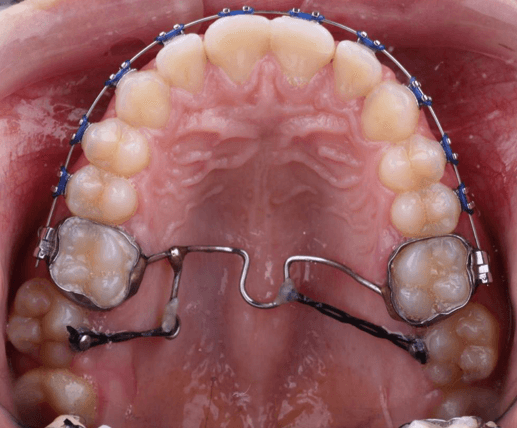

11 de junio de 2024 – Activación superior y colocación del ATP modificado

Se realizó el primer ajuste del arco superior. Se cementó el arco transpalatino modificado (ATP) con ganchos distales adicionales en ambos extremos. En las caras palatinas de los órganos dentarios 17 y 27 se colocaron botones de tracción, desde los cuales se fijaron cadenas elásticas hasta los ganchos del ATP. Se mantuvo el mismo arco superior NiTi 0.014".

20 de agosto de 2024 – Activación del ATP y colocación inferior

Se activó el ATP mediante reposición y ajuste de cadenas elásticas, específicamente desde el omega izquierdo del ATP. Se mantuvo el arco superior NiTi 0.016". Se procedió a la colocación del sistema de brackets en el arco inferior (SAP) y se instaló un arco inferior de NiTi calibre 0.014".